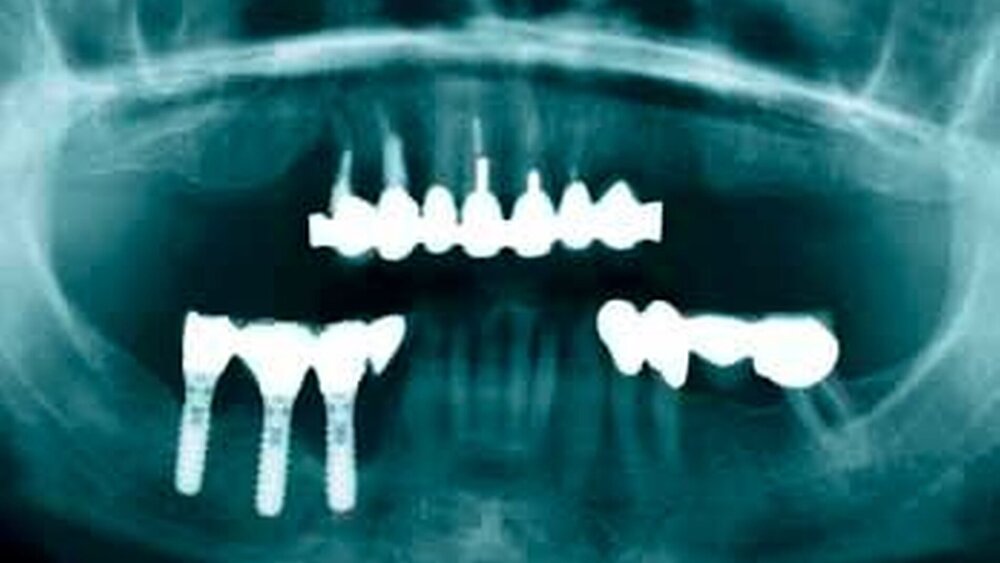

Entsprechend dem Tagungsthema „Der gelockerte Zahn – das gefährdete Implantat“ war die Jahrestagung insbesondere den Gemeinsamkeiten und Unterschieden zwischen der Parodontitis und der Periimplantitis gewidmet. Obwohl Implantate bereits seit vielen Jahren eine Bereicherung des parodontologischen Behandlungsspektrums darstellen, sind auch Implantate wie natürliche Zähne von bakteriellen Infektionen und Knochendestruktion betroffen. Aus diesem Grunde sind die frühzeitige Diagnose und Therapie einer Periimplantitis sowie Maßnahmen zu deren Prävention essentiell.

Den Kongressteilnehmern konnte Tagungspräsident Prof. Dr. Dr. Søren Jepsen, Bonn, ein spannendes Wissenschaftsprogramm präsentieren. Bereits im Vorfeld der Tagung hatte er darauf hingewiesen, dass Parodontalerkrankungen in den meisten Fällen erfolgreich therapiert werden können, während andererseits Implantate, die parodontal erkrankte Zähne ersetzen, langfristig in ihrer Integrität ebenfalls durch die mögliche Entwicklung einer chronischen periimplantären Entzündung bedroht sind. Daher sei das Implantat nicht per se die bessere und problemlosere Alternative zum parodontal erkrankten Zahn. Bei der Abwägung zwischen Zahnerhaltung durch systematische Parodontaltherapie und Extraktion mit nachfolgender Implantation sollte diese Jahrestagung eine hilfreiche Orientierung geben. Namhafte Experten aus dem In- und Ausland referierten über Themen von hoher klinischer Relevanz und zeigten die Zukunftsperspektiven im Bereich der Parodontologie sehr überzeugend auf.

Als erster Vortragender ging Prof. Niklaus Lang, Bern, Schweiz, Ehrenmitglied der DGP und Editor von Clinical Oral Implants Research, in seinem Vortrag auf die ätiologischen und pathogenetischen Gemeinsamkeiten zwischen Periimplantitis und Parodontitis ein. Prof. Lang legte dar, dass sich die Periimplantitis trotz einiger struktureller Unterschiede nicht von der Parodontitis unterscheidet. Die Gewebereaktion auf den mikrobiellen Angriff fällt jedoch im periimplantären Gewebe stärker aus. Unbehandelt schreitet eine Periimplantitis voran. Da parodontale Resttaschen die Besiedelung der Implantate mit pathogenen Mikroorganismen fördern, forderte der Referent, dass erst nach erfolgreicher Parodontitistherapie Implantate gesetzt werden sollten.

Pathogene Keime besiedeln direkt nach Implantation

Die mikrobiologischen Aspekte bei der Ätiopathogenese und Therapie der Periimplantitis wurden von Prof. Andrea Mombelli, Genf, Schweiz, erläutert. Die periimplantäre Flora etabliert sich bereits kurz nach Insertion des Implantats. Zudem können parodontalpathogene Mikroorganismen bei Parodontitispatienten auf das Implantat übertragen werden. Die Vor- und Nachteile bei der Therapie der Periimplantitis mit Küretten, Ultraschall, Pulverstrahl und Laser wurden besprochen. Prof. Mombelli ging außerdem auf die Unterstützung der antiinfektiösen Behandlung mittels lokaler und systemischer Antibiotikatherapie ein. Der Referent schlussfolgerte, dass die Reinigung und antimikrobielle Therapie der periimplantären Taschen trotz eingeschränkten Zugangs und rauer Implantatoberfläche zumindest kurzfristig zu einer Verbesserung der klinischen Situation führen kann. Bisher fehlen jedoch noch Langzeitdaten über die Wirksamkeit der antiinfekiösen Therapien und Studien, die die verschiedenen Therapieverfahren miteinander vergleichen.

Prof. Stefan Renvert, Kristianstad, Schweden, berichtete über aktuelle Daten aus Langzeitstudien, die eine hohe Prävalenz der Periimplantitis bei bis zu 16 Prozent der Patienten aufzeigen konnten. Gegenwärtige Therapiemöglichkeiten der Periimplantitis basieren zu einem Großteil auf den in der Parodontaltherapie gesammelten Erfahrungen. Häufig werden Kombinationsbehandlungen, die darauf abzielen, die Bakterienbesiedelung in den periimplantären Taschen mechanisch, chemisch oder durch Laser zu reduzieren, durchgeführt. Prof. Renvert wies darauf hin, dass die periimplantären Gewebe nach der Beseitigung der bakteriellen Besiedelung die Fähigkeit zur Heilung aufweisen. Einige tierexperimentelle und klinische Studien konnten zeigen, dass nach einer chirurgischen Reinigung der infizierten Implantatoberfläche und augmentativen chirurgischen Verfahren eine erneute Knochenadaptation erfolgen kann.

Prof. Maurizio Tonetti, Genua, Italien, Ehrenmitglied der DGP und Editor des Journal of Clinical Periodontology, verglich in seinem Abschlussvortrag die Prognose von Zähnen und Implantaten bei Parodontitispatienten. Der Referent wies daraufhin, dass solch ein Vergleich nur realistisch ist, wenn man die Erfolgsrate der zumeist vor Implantation stattfindenden Knochenaugmentation mit einbezieht. Prof. Tonetti konnte anhand aktueller Daten überzeugend dokumentieren, dass die „kombinierte“ Erfolgsrate für Knochenaugmentation und Implantat nicht besser ist als für natürliche Zähne. Zusätzlich unterscheiden sich die Risikofaktoren für Periimplantitis (Mundhygiene, Rauchen, Systemerkrankungen, genetische Disposition) nicht von denen für Parodontitis. Dies erklärt auch, warum das Risiko für Periimplantitis bei Patienten, die parodontal erkrankt waren, erhöht ist. Der Unterschied zwischen parodontal erkrankten und gesunden Patienten bezüglich der Implantatüberlebensrate wird jedoch erst nach den ersten fünf bis sechs Jahren deutlich. Zusammenfassend schlussfolgerte Tonetti, dass Zähne ähnlich wie Implantate bei Parodontitispatienten abschneiden, und dass die Empfänglichkeit für Periimplantitis mit derjenigen für Parodontitis sehr eng assoziiert ist. Nicht die Entscheidung für Parodontitistherapie oder Implantation, sondern deren Kombination, eingebunden in ein parodontologisch orientiertes Betreuungskonzept, stellt die optimale Therapie dar.

Auf der DGP-Jahrestagung fanden außerdem elf Workshops statt, die sich den unterschiedlichsten Bereiche der Parodontologie, wie Laseranwendung, antimikrobielle photodynamische Therapie, Sofortimplantation, antiinfektiöse und minimalinvasive Parodontitistherapie, plastisch-ästhetische Parodontalchirurgie und Tabakentwöhnung, widmeten. In einem dieser Workshops referierte Priv.-Doz. Frank Schwarz, Düsseldorf, sehr umfassend über aktuelle Aspekte in Diagnostik und Therapie der periimplantären Infektion. Der Referent wies darauf hin, dass im Unterschied zu parodontalen Läsionen der periimplantäre Knochendefekt zirkulär sei und mit einer Metall- oder Kunststoffsonde gemessen werden sollte. Zur Therapie gehöre die Entfernung des mikrobiellen Biofilms, wobei er anhand umfangreicher eigener Studien den Er:YAG-Laser favorisierte. Die chirurgische Therapie kann resektive aber auch augmentative Verfahren beinhalten (wie Implantatplastik, autologer Knochen mit/ohne Kollagenmembran). Die Möglichkeit einer echten Reosseointegration nach Dekontamination der Implantatoberflächen wurde allerdings nicht nur von PD Dr. Schwarz, sondern auch von Prof. Jürgen Becker, Düsseldorf, in seinem Symposiumsvortrag bezweifelt. Somit käme bei einer fortgeschrittenen Periimplantitis nur die Explantation infrage, wobei die Bereitschaft der Patienten für eine solche Maßnahme oft sehr gering sei.